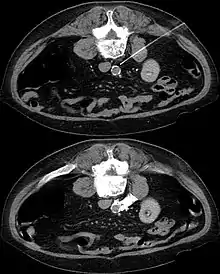

In CT guided lumbar sympathicolysis, the site of neurolytic solution injection is chosen at the level of L2-L3 vertebra level. The needle should avoid the vertebral transverse process, ureter, pelvicalyceal system, and other major blood vessels. The target injection site would be anteromedial to the psoas muscle and dorsolateral to the abdominal aorta, where the sympathetic trunk would most likely be located.[1]

After the skin of the puncture site is cleaned, 2% lignocaine is injected into the to numb the skin and also the needle trajectory. Then a 22G China needle is inserted into the target site, which is bounded by the vertebral body, aorta, inferior vena cava, and psoas muscle. This region houses the lumbar sympathetic ganglion. Then, iodinated contrast medium (iohexol) and lignociane is injected into the target site to check the position of the needle tip. Once the needle tip position is confirmed, a mixture of neurolytic solution (99.9% alcohol) and iodinated contrast medium (at a ratio of 10:1) is injected into the target site.[1]